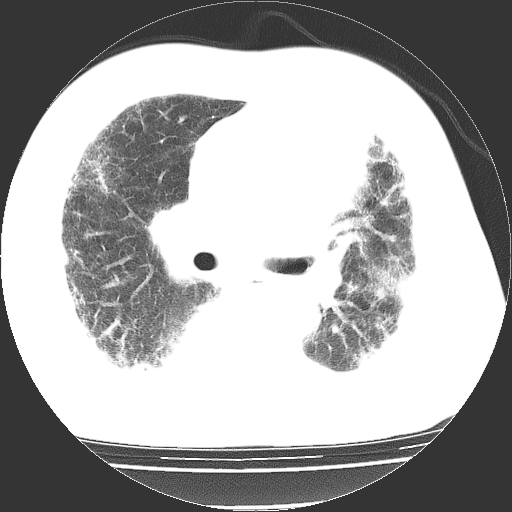

男,68岁,咳嗽、胸闷、发烧三天,查体:双肺散在湿罗音。

依据:1、两肺广泛条索状、网格状、蜂窝状改变。

双肺多发条索状、网格状及小灶状密度增高影。考虑慢支合并感染.间质纤维化,双侧少量胸腔积液

两肺广泛条索状、网格状、蜂窝状改变。肺间质纤维化,肺心病,双侧胸腔积液